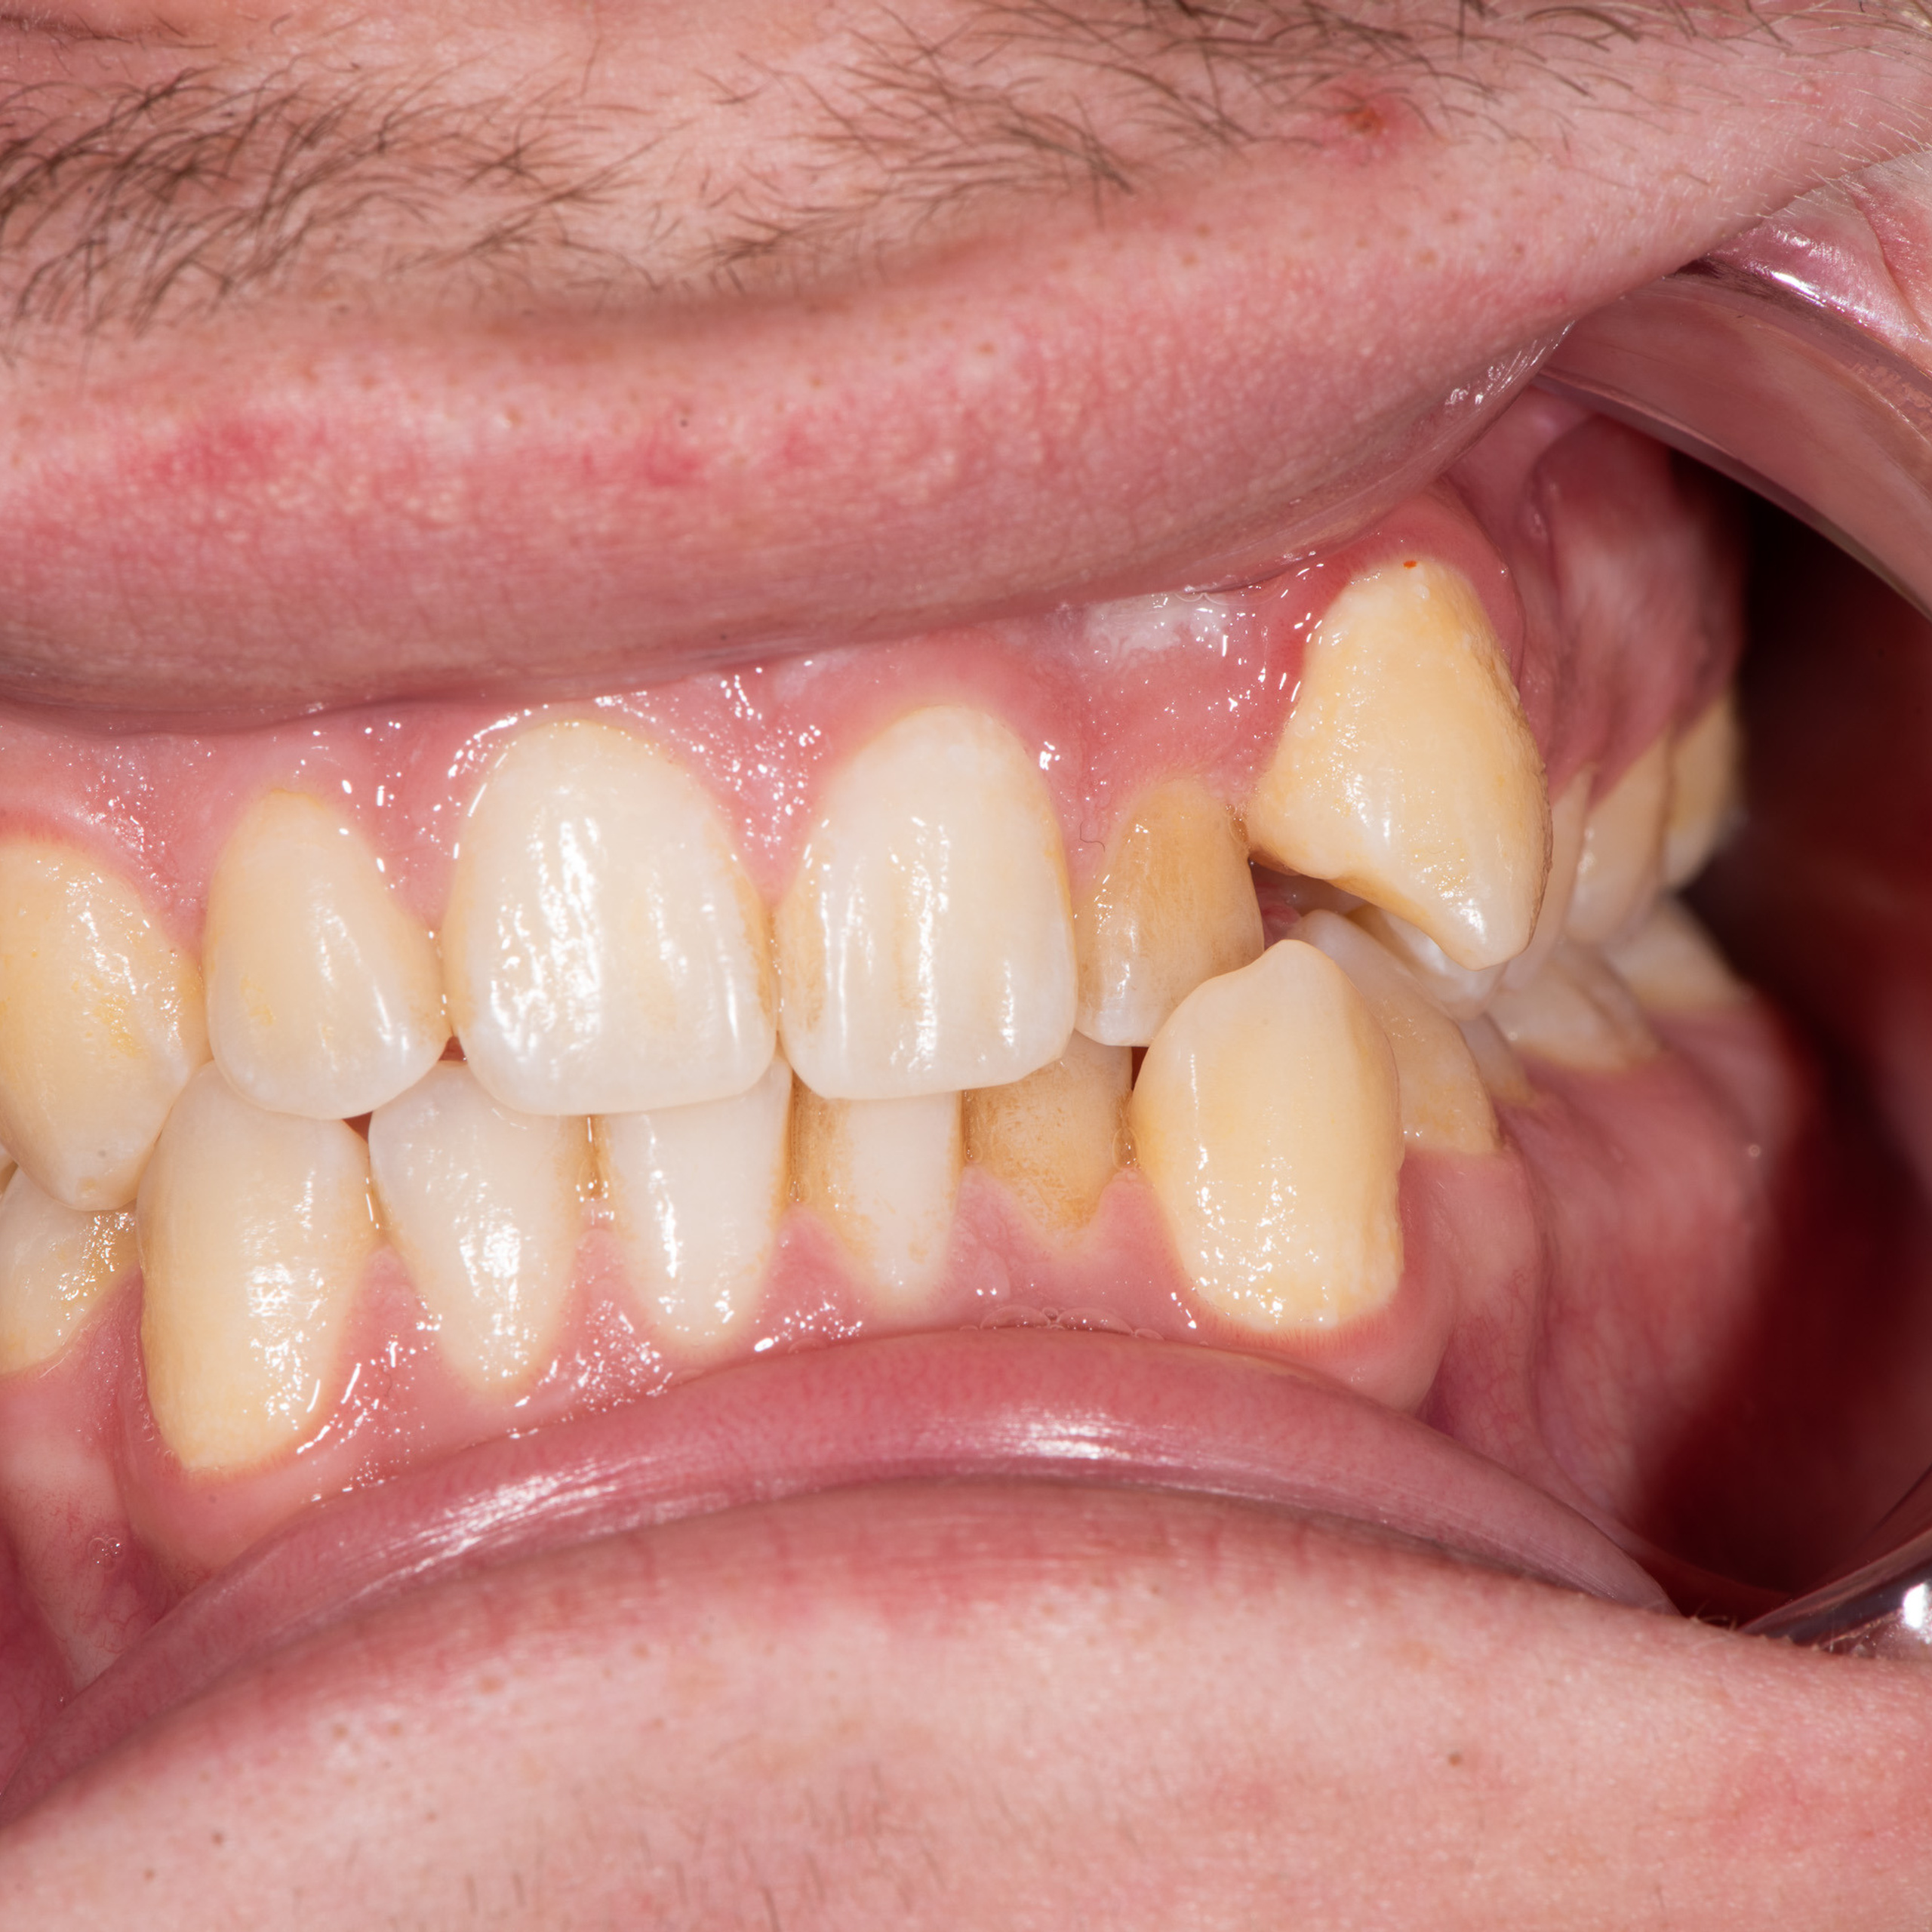

Фотографии учеников до обучения